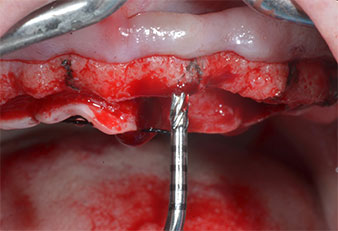

Пиезоелектрически инструмент с диамантено покритие с форма на пламък (Piezomed I1) e използван за маркиране на позициите на имплантите и за пилотна подготовка (Фиг. 3). Препарацията беше извършена с внимателни вертикални движения, с намалена мощност, пълна иригация и лек натиск (под 300 g) След това се приложи пилотен инструмент (Piezomed I2A/ I2P) за първоначално увеличение на диаметъра на имплантното ложе с 2 mm (Фиг. 4), последвано от 3 mm разширение (Фиг. 5)

В случай на твърда кост, цялата поредица от инструменти, включително междинните инструменти Piezomed Z25P и Z35P, трябва да се използват за разширяване на остеотомиите.

Те също така са предназначени за подготовка в близост до синусовата мембрана във връзка с вътрешни аугметационни процедури или когато има по-малко от 4 mm остатъчна височина на костта.

В настоящия случай инструменти Z25P и Z35P не са използвани поради сравнително меката задна кост, която лесно се обработва с I3A/I3P.